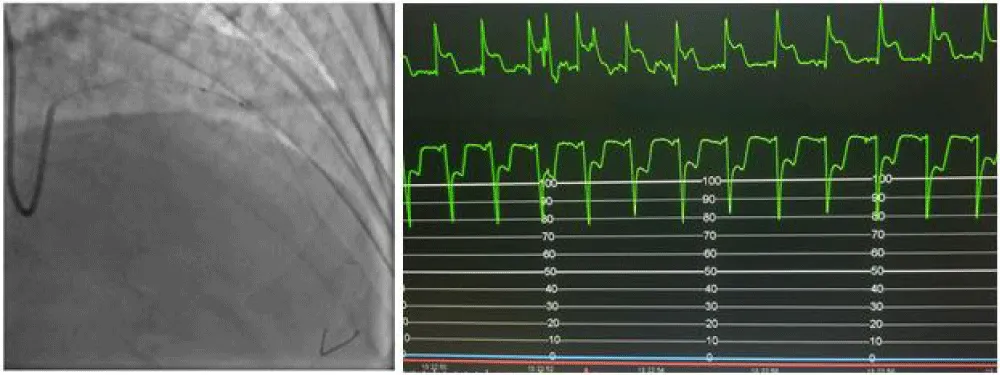

We gradually removed this emergency assembly that allowed us to release and retrieve the trapped balloon (Figure 5). The control injection revealed a thrombotic occlusion of the LAD treated by thrombectomy and anti-GPIIbIIIa followed by a DES 2.75% 28 placement that allows a TIMI III flow in the LAD at the cost of losing the small diagonal artery that we could not recross (Figure 6).

Figure 5: Trapped balloon retrieval.

Figure 6: Management of the thrombotic occlusion of the LAD and result (A: Thrombectomy and balloon. B: result. C: ST regression. D: Stenting DES 2.75x28. E: Final result. F: Diagonal before PCI).

The patient remained stable after the procedure with normalization of his ECG and LVEF at 58% and was discharged 48 hours later.